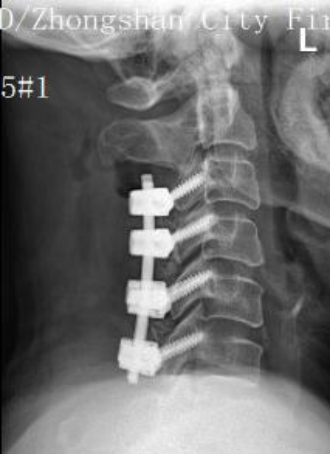

手術(shù)由程俊杰主任醫(yī)師主刀,在麻醉科和手術(shù)室的通力配合下,專家團(tuán)隊(duì)運(yùn)用超聲骨刀進(jìn)行了精準(zhǔn)截骨減壓。術(shù)中有效擴(kuò)大了狹窄的椎管,為受損的脊髓神經(jīng)創(chuàng)造了寶貴的復(fù)蘇空間。隨后,團(tuán)隊(duì)順利置入側(cè)塊螺釘內(nèi)固定系統(tǒng),位置精準(zhǔn)、固定牢靠,并進(jìn)行了關(guān)節(jié)突關(guān)節(jié)植骨融合。

術(shù)后X光片側(cè)位